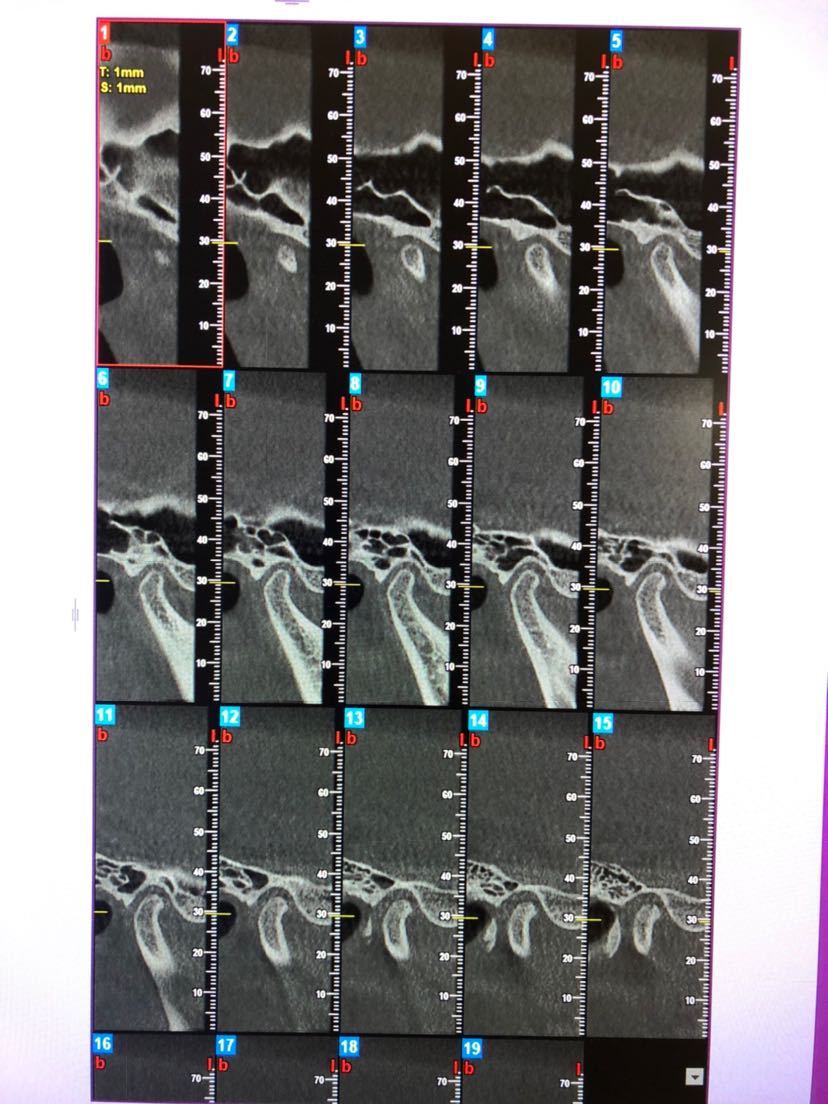

颞下颌关节紊乱双侧不可复位

图片尺寸1080x1439